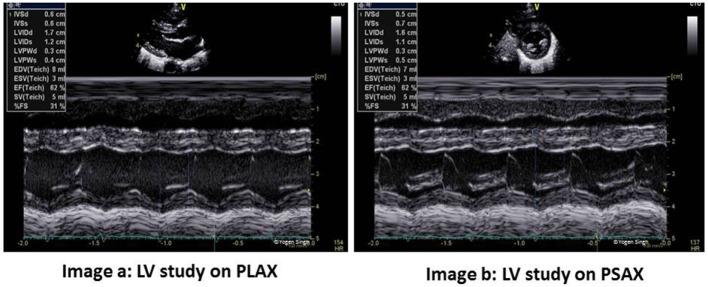

Hemodynamic instability and inadequate cardiac performance are common in critically ill children. The clinical assessment of hemodynamic status is reliant upon physical examination supported by the clinical signs such as heart rate, blood pressure, capillary refill time, and measurement of the urine output and serum lactate. Unfortunately, all of these parameters are surrogate markers of cardiovascular well-being and they provide limited direct information regarding the adequacy of blood flow and tissue perfusion. A bedside point-of-care echocardiography can provide real-time hemodynamic information by assessing cardiac function, loading conditions (preload and afterload) and cardiac output. The echocardiography has the ability to provide longitudinal functional assessment in real time, which makes it an ideal tool for monitoring hemodynamic assessment in neonates and children. It is indispensable in the management of patients with shock, pulmonary hypertension, and patent ductus arteriosus. The echocardiography is the gold standard diagnostic tool to assess hemodynamic stability in patients with pericardial effusion, cardiac tamponade, and cardiac abnormalities such as congenital heart defects or valvar disorders. The information from echocardiography can be used to provide targeted treatment in intensive care settings such as need of fluid resuscitation versus inotropic support, choosing appropriate inotrope or vasopressor, and in providing specific interventions such as selective pulmonary vasodilators in pulmonary hypertension. The physiological information gathered from echocardiography may help in making timely, accurate, and appropriate diagnosis and providing specific treatment in sick patients. There is no surprise that use of bedside point-of-care echocardiography is rapidly gaining interest among neonatologists and intensivists, and it is now being used in clinical decision making for patients with hemodynamic instability. Like any other investigation, it has certain limitations and the most important limitation is its intermittent nature. Sometimes acquiring high quality images for precise functional assessment in a ventilated child can be challenging. Therefore, it should be used in conjunction with the existing tools (physical examination and clinical parameters) for hemodynamic assessment while making clinical decisions.

血流动力学不稳定和心脏功能不全在危重症儿童中很常见。血流动力学状态的临床评估依赖于体格检查,并辅以心率、血压、毛细血管再充盈时间等临床体征,以及尿量和血清乳酸的测量。不幸的是,所有这些参数都是心血管健康的替代指标,它们提供的关于血流充足性和组织灌注的直接信息有限。床旁即时超声心动图可以通过评估心脏功能、负荷状态(前负荷和后负荷)和心输出量来提供实时血流动力学信息。超声心动图能够实时提供纵向功能评估,这使其成为监测新生儿和儿童血流动力学评估的理想工具。它在休克、肺动脉高压和动脉导管未闭患者的管理中不可或缺。超声心动图是评估心包积液、心脏压塞以及先天性心脏病或瓣膜疾病等心脏异常患者血流动力学稳定性的金标准诊断工具。超声心动图提供的信息可用于在重症监护环境中进行针对性治疗,如确定是否需要液体复苏还是使用血管活性药物支持、选择合适的血管活性药物或血管加压药,以及在肺动脉高压中提供特定干预措施,如选择性肺血管扩张剂。从超声心动图收集的生理信息可能有助于对患病患者做出及时、准确和适当的诊断并提供特定治疗。毫不奇怪,床旁即时超声心动图的使用在新生儿科医生和重症监护医生中迅速受到关注,现在它正被用于血流动力学不稳定患者的临床决策。与任何其他检查一样,它有一定的局限性,最重要的局限性是其间歇性。有时,在通气的儿童中获取高质量图像以进行精确的功能评估可能具有挑战性。因此,在做出临床决策时,应将其与现有的血流动力学评估工具(体格检查和临床参数)结合使用。